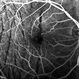

- Hypotony maculopathy in uveitis

- hypotony, hypotony maculopathy, uveitis

- 20 y.o male with hypotony (4 mmHg) caused by cilliary body shutdown in setting of anterior uveitis.